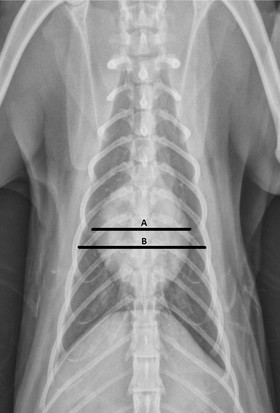

Изобр 1.Оценка процента ширины грудной клетки (A/B) на этой вентродорсальной проекции был выполнен при помощи оценки ширины силуэта сердца (A) как части ширины грудной клетки (B), на уровне, где силуэт сердца максимальной широкий. Этот метод был выполнен тем же способом для дорсовентральных проекций.